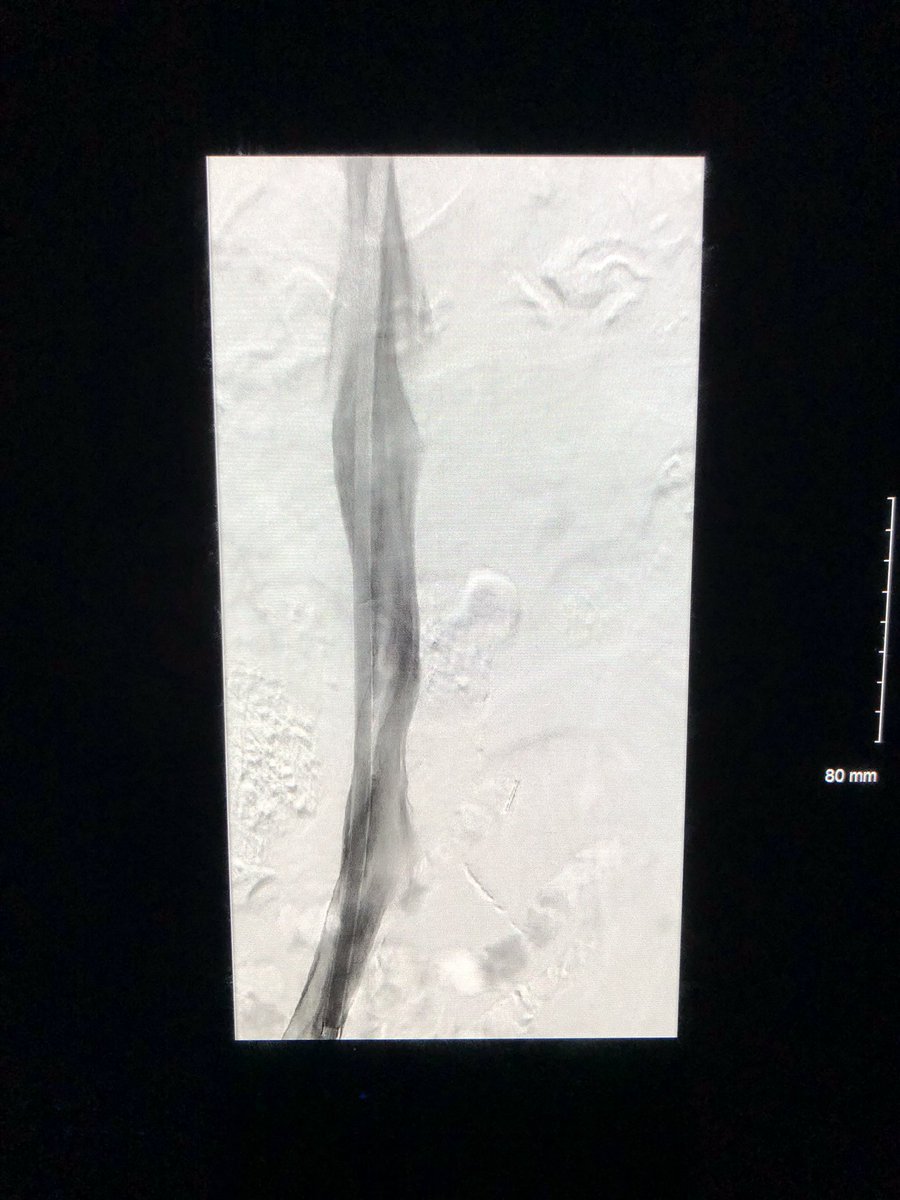

This patient presented with severe leg edema, iliocaval thrombus with 12 year old #IVCfilter. After a night of lysis a large vol of chronic appearing clot persisted. Was able to get most of it out with a few passes with the Inari T20 from popliteal access. #iRad